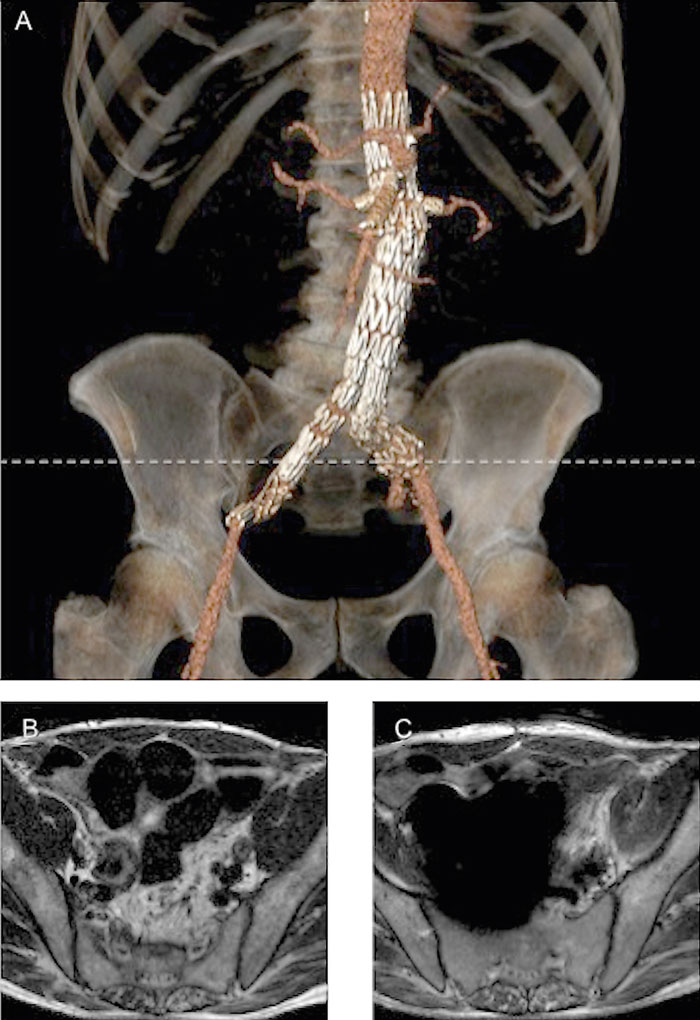

Det reella problemet med ett stentgraft är inte risken för att orsaka patienten skada utan i stället de bildartefakter som uppstår vid MR-undersökningen. Eftersom artefakternas utbredning skiljer sig så mycket mellan materialen nitinol och rostfritt stål typ 304 [11] är det viktigt att veta vilket material som är aktuellt när man ska ta ställning till en MR-undersökning. Artefakter framkallade av rostfritt stål typ 304 är så pass omfattande att avbildning av stora delar av överkroppen påverkas. Påverkan på bildkvaliteten är däremot mycket begränsad med nitinol (Figur 2), och enligt en fantomstudie [11] ska det till och med vara möjligt att följa upp det endovaskulära ingreppet.

Utifrån tillgänglig information och erfarenhet är vår slutsats att patienter med stentgraft utan risk för skada kan genomgå MR-undersökningar med 1,5 T- och 3,0 T-system direkt efter implantationen utan restriktioner. Avseende bildkvalitet är det viktigt att ta hänsyn till att stentgraft tillverkade av rostfritt stål typ 304 orsakar mycket kraftiga artefakter och släcker ut signalen inom en radie av 20 cm eller mer från implantatet. För stentgraft tillverkade av nitinol är artefakterna i stället ca 1 cm eller mindre från implantatet, vilket innebär att det är möjligt att med MR-kamera svara på frågeställningar om ryggmärgspåverkan och bäckentumörspridning.

Figur 2. Patient behandlad med EVAR. Stentgraft av nitinol. A: Axialt snitt från DT-undersökning. Röd pil = stentgraft, blå pil = metallclips. B: Axialt snitt från MR-undersökning i motsvarande läge. Det framgår tydligt att clipset ger upphov till kraftigare störningar än stentgraftet. C: Axialt snitt från MR-undersökning något kranialt om de två andra snitten.  MR-bilderna togs vid 1,5 T med en THRIVE-sekvens efter kontrastinjektion.